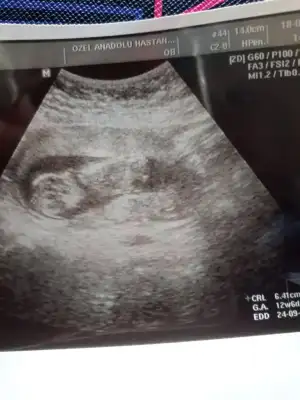

Kızlar sizce cinsiyeti ne lütfen söyleyin sanırım ok'la gösterilen kısım genital bölge

Eklentiler